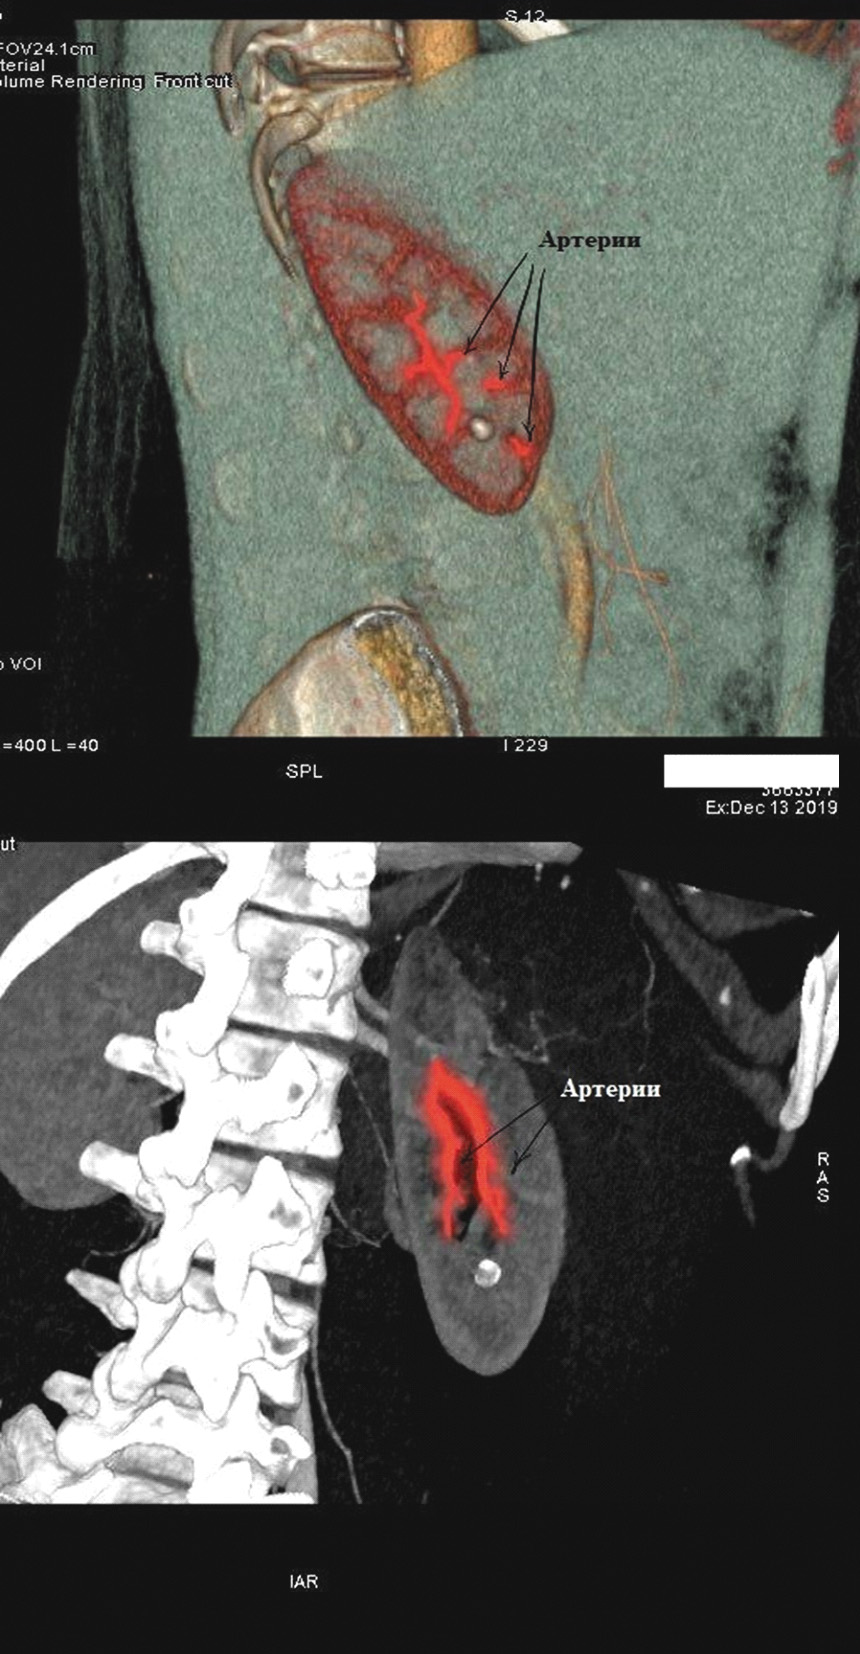

Нами были изучены результаты 60 мини-перкутанных литотрипсий. Все они проводились с использованием 3D-планирования доступа в программах «Автоплан», «Луч-С» и VessellQ Xpress. При нативном и отсроченном сканировании находили целевую группу чашечек, содержащую конкремент. В артериальную фазу определяли тип кровоснабжения почки и ее малососудистые зоны (рисунки 1, 2).

Рисунок 1. Определение строения артериального русла почки (артерии выделены дополнительно).

Рисунок 2. Определение малососудистой зоны (артерии выделены дополнительно).